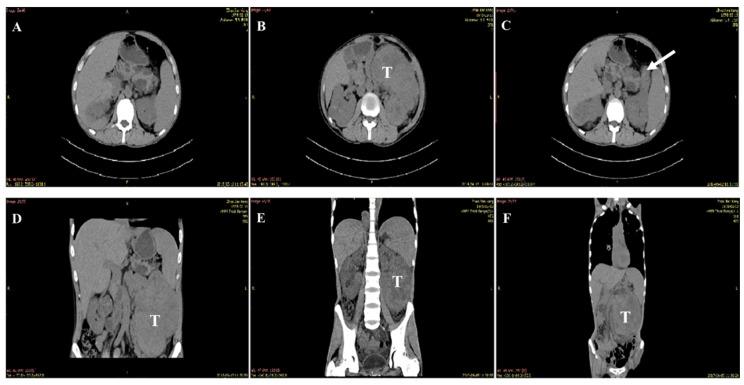

Von Hippel-Lindau (VHL) genes are intimately involved in renal cell carcinoma (RCC), including clear cell RCC (ccRCC) pathogenesis. However, the contribution of pathogenic VHL mutations to ccRCC remains poorly understood. We report a xanthoderm with non-obstructive azoospermia (NOA)-associated cystic ccRCC, and the missense VHL mutation (c.262T > C, p.Try88Arg). In a 34-year-old patient, a urologic physical examination identified hard epididymis, and imaging tests revealed deferens-associated NOA, as well as multi-organ hydatid cysts, including bilateral epididymal cysts, bilateral testicular cysts, bilateral renal cysts, and pancreatic cysts. Five years later, ccRCC was developed based on clinical and radiologic evidence. Two different prediction models of protein structure and multiple sequence alignment across species were applied to assess the pathological effects of the VHL mutation. The reliability of the assessment in silico was determined by both the cellular location and protein levels of the mutant products, using IF and Western blot, respectively. Our study shows that the missense VHL mutation (c.262T > C, p.Try88Arg) plays a deleterious role in pVHL functions, as predicted by multiple sequence alignment across species. While a structural analysis identified no significant structural alterations in pVHL, the detrimental effects of this mutation were determined by exogenous expression, evidenced by a markedly different spatial distribution and reduced expression of mutant pVHL. This is the first report of the VHL gene mutation (c.475T > C, p.Try88Arg) in a xanthoderm.

冯·希佩尔-林道(VHL)基因与肾细胞癌(RCC)密切相关,包括透明细胞 RCC(ccRCC)的发病机制。然而,致病性 VHL 突变对 ccRCC 的贡献仍知之甚少。我们报告了一例伴有非梗阻性无精子症(NOA)相关囊性 ccRCC 的黄瘤病,以及错义 VHL 突变(c.262T > C,p.Try88Arg)。在一名 34 岁的患者中,泌尿科体格检查发现硬附睾,影像学检查显示与输精管相关的 NOA,以及多器官包虫囊肿,包括双侧附睾囊肿、双侧睾丸囊肿、双侧肾囊肿和胰腺囊肿。五年后,根据临床和影像学证据诊断为 ccRCC。应用两种不同的蛋白质结构预测模型和跨物种多序列比对来评估 VHL 突变的病理影响。通过免疫荧光和 Western blot 分别评估突变产物的细胞定位和蛋白水平,确定了体外评估的可靠性。我们的研究表明,错义 VHL 突变(c.262T > C,p.Try88Arg)在跨物种多序列比对预测的 pVHL 功能中具有有害作用。虽然结构分析未发现 pVHL 结构发生显著改变,但通过外源性表达确定了该突变的有害影响,突变型 pVHL 的空间分布明显不同,表达水平降低。这是首例黄瘤病中 VHL 基因突变(c.475T > C,p.Try88Arg)的报道。